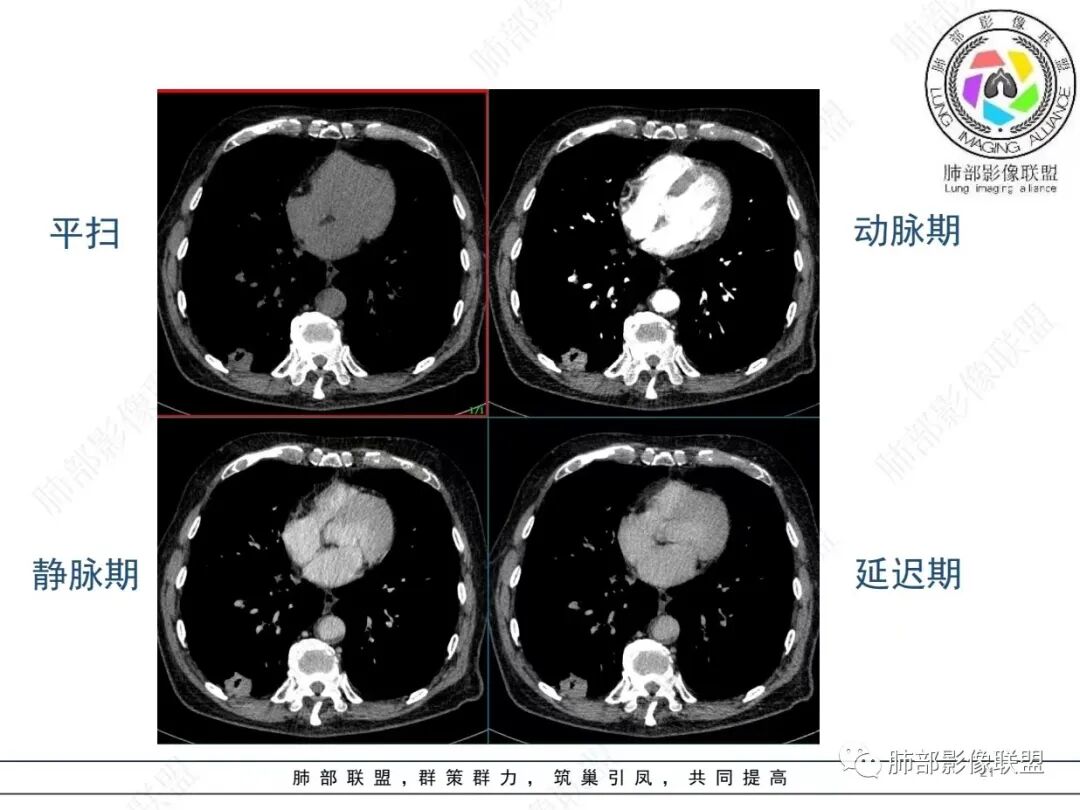

老年男性,发作性气喘,实验室检查白细胞增高。肺部影像表现:右肺胸膜下占位性病变,肺气肿背景,内部可见空腔/空泡影,周围可见小结节,增强动脉期明显强化,静脉期及延迟期强化减低,右侧肺门可见肿大淋巴结,有吸烟史,近年减少,首先考虑恶性肿瘤,肺小细胞癌/鳞癌,隐球菌作为鉴别诊断,病例穿刺活检。

老年男性,气短,胸痛半年,考虑慢性病史,无发热,常见的肺部感染可以排除,右肺下叶基地段靠近胸膜实变影,边缘清楚,不均匀强化,可见空泡征,点状血管影,周围小叶中央型结节,有网格影,支气管扩张,磨玻璃影,肺间质改变,右侧肺门淋巴结肿大,综合考虑恶性肿瘤并肺内转移

老年男性,肺气肿背景,右肺下叶,右肺下叶胸膜处实性结节,形似山丘,有分叶,病灶内可见扩张细支气管/空泡,边缘可见弯曲血管,增强后不均匀强化,可见血管影,病灶胸膜侧呈小波浪??状,局部突入胸膜面,右肺门肿大淋巴结。考虑恶性结节,小细胞肺癌,腺癌,鉴别炎性肉芽肿。建议ct下穿刺活检。

老年男性,肺气肿病史,支气管束增粗,管壁增厚,右肺下叶后基底段胸膜下肿块,土豆征,边界清,有膨隆,小支气管边缘阻断,见集血管束征,肿块强化明显(快进快出特点),并偏心空洞,胸膜下栽赃,周围肺结构破坏(蜂窝状影表现),右肺门淋巴结转移肿大,血管内皮生长因子偏高,肿块与小支气管,血管束关系密切,强化特点,定恶性肺肿瘤,小细胞Ca。

老年男性,肺气肿,右肺下叶胸膜下结节,边缘毛躁,周围多发间质增厚,临近胸膜下脂肪间隙模糊,增强后动脉期不均匀强化,延迟期强化较低,右肺门肿大淋巴结,考虑恶性,鳞癌,小细胞肺癌,鉴别炎性肉芽肿性结节

右下叶胸膜下结节,宽基底与胸膜相连,结节与胸膜相交呈钝角〈山丘征〉,内可见充气扩张的支气管,中度强化,结节边缘无毛刺,内见走行自然的血管影,提示破坏力及收缩力差,右肺门可见肿大淋巴结,老年烟民,考虑恶性占位,支持小细胞癌

右肺下叶胸膜下结节,呈山丘状,生长在慢支肺气肿间质纤维化的基础上,边缘相对光滑清晰,右肺门淋巴结肿大,强化呈速升速降,老年男性,吸烟史,考虑小细胞肺癌,鉴别隐球

恶性明确(右肺门淋巴结明显肿大,中心坏死,坏死边界不清楚,胸膜下馒头样肿块,血管集束,支气管阻塞,动脉期明显强化,内部明确的供血血管提示肿瘤细胞密集,局部坏死边界不清,强化快进快出,邻近胸膜强化呈胸膜尾征,提示胸膜受侵),病理符合周围性低分化鳞癌(老年男性,长期吸烟史,肿块强化明显,快进快出,坏死边界不清楚,阻塞性炎症及阻塞性肺气肿,肺门淋巴结肿大,坏死,邻近支气管壁增厚支持粘膜下侵润生长),白细胞总数高,动脉期强化那么明显,腺癌合并感染倒是要高度警惕。

老年男性,吸烟史+肺气肿背景,右下肺胸膜下肿块(坏死+内部血管影+快进快出),右侧肺门淋巴结肿大,考虑:恶性、鳞?高级别腺待排(总体感觉偏软)。

男,80,发作性气喘半年,加重1天。长年大量吸烟史。肺部CT:肺气肿背景,右肺胸膜下实性占位,处于外周大疱带与气肿带交界,山丘征,边缘膨隆,边界较清,血管集束,周围可见小结节。增强不均匀强化,内可见迂曲模糊血管影,右肺门、隆突下可见肿大淋巴结。首先考虑恶性肿瘤,小?鳞?鉴别PC、TB等。